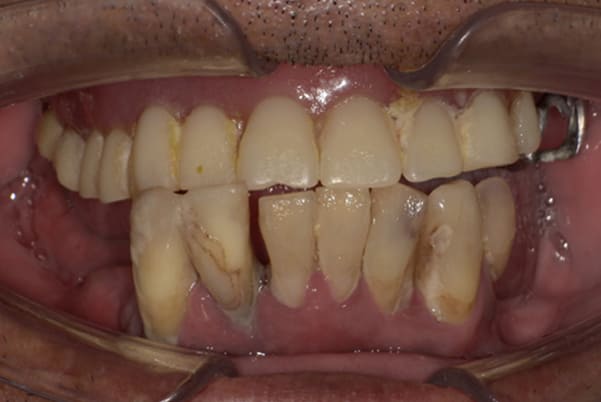

上下互い違いで咬む歯同士がない状態のため、柔らかいものを舌で潰され召し上がっておられました。

かみ合わせがなく、すれ違い咬合と言われる難症例に分類される状態でした。

上の歯は重度歯周炎でぐらぐらで、お痛みも繰り返しており、抜歯が必要な状態でした。

検査の結果、下の3本のうち、2本は何とか根は残せる状態であったため、虫歯の治療、根の治療を行い残すことに努めました。

上下の歯同士のかみ合わせがない状態で長年過ごされていましたので、当初はどこで咬んだら良いかわからない状態でしたが、治療用入れ歯を用い、調整を行い、本来のかみ合わせに戻すことが可能になりました。